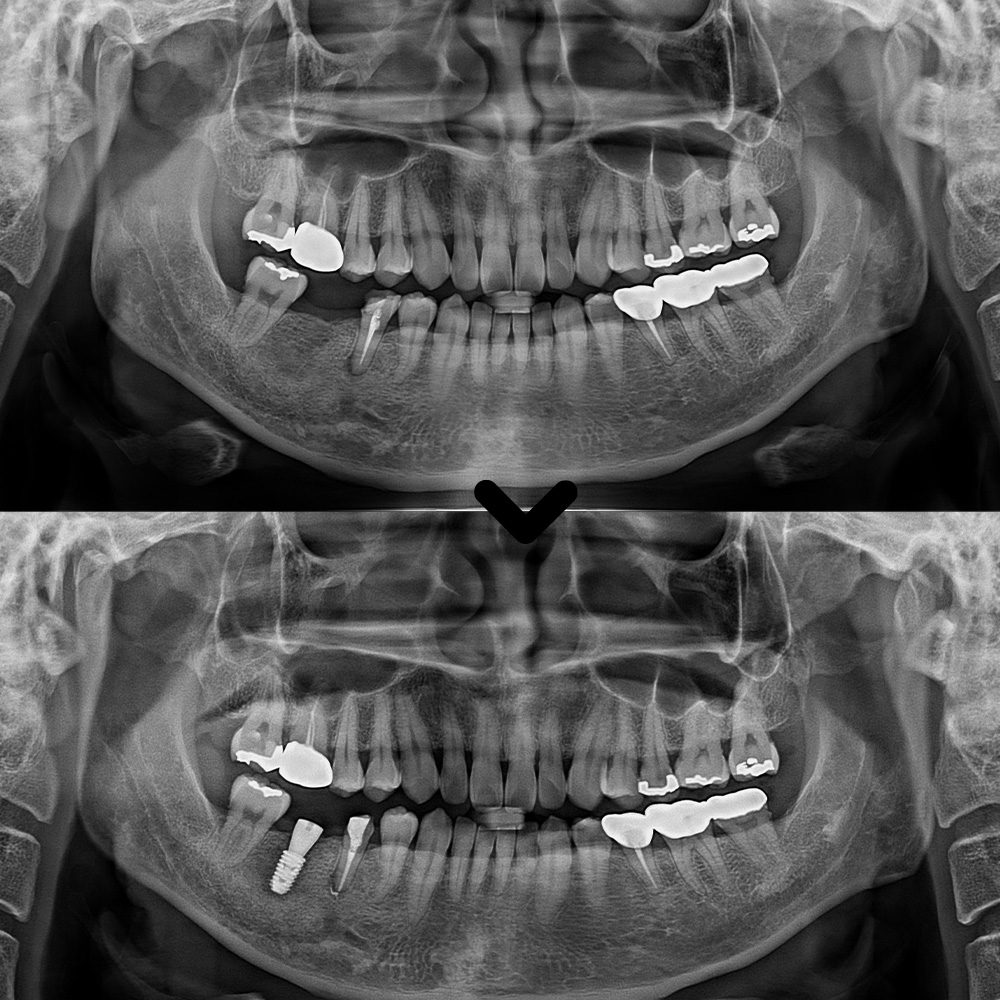

치료 후 엑스레이 촬영을 통해

확인한 결과,

뿌리 끝 염증이 이전보다

눈에 띄게 감소한 것을

확인할 수 있었습니다.

이렇게 앞 치아 마무리 후

뒤 치아의 무절개 임플란트

식립을 진행하였습니다.

이렇게 임플란트 식립 후

치유기간을 거친 뒤

2개월 후에 최종 임플란트 보철을

세팅해 드렸습니다.

마무리 후 사진입니다.